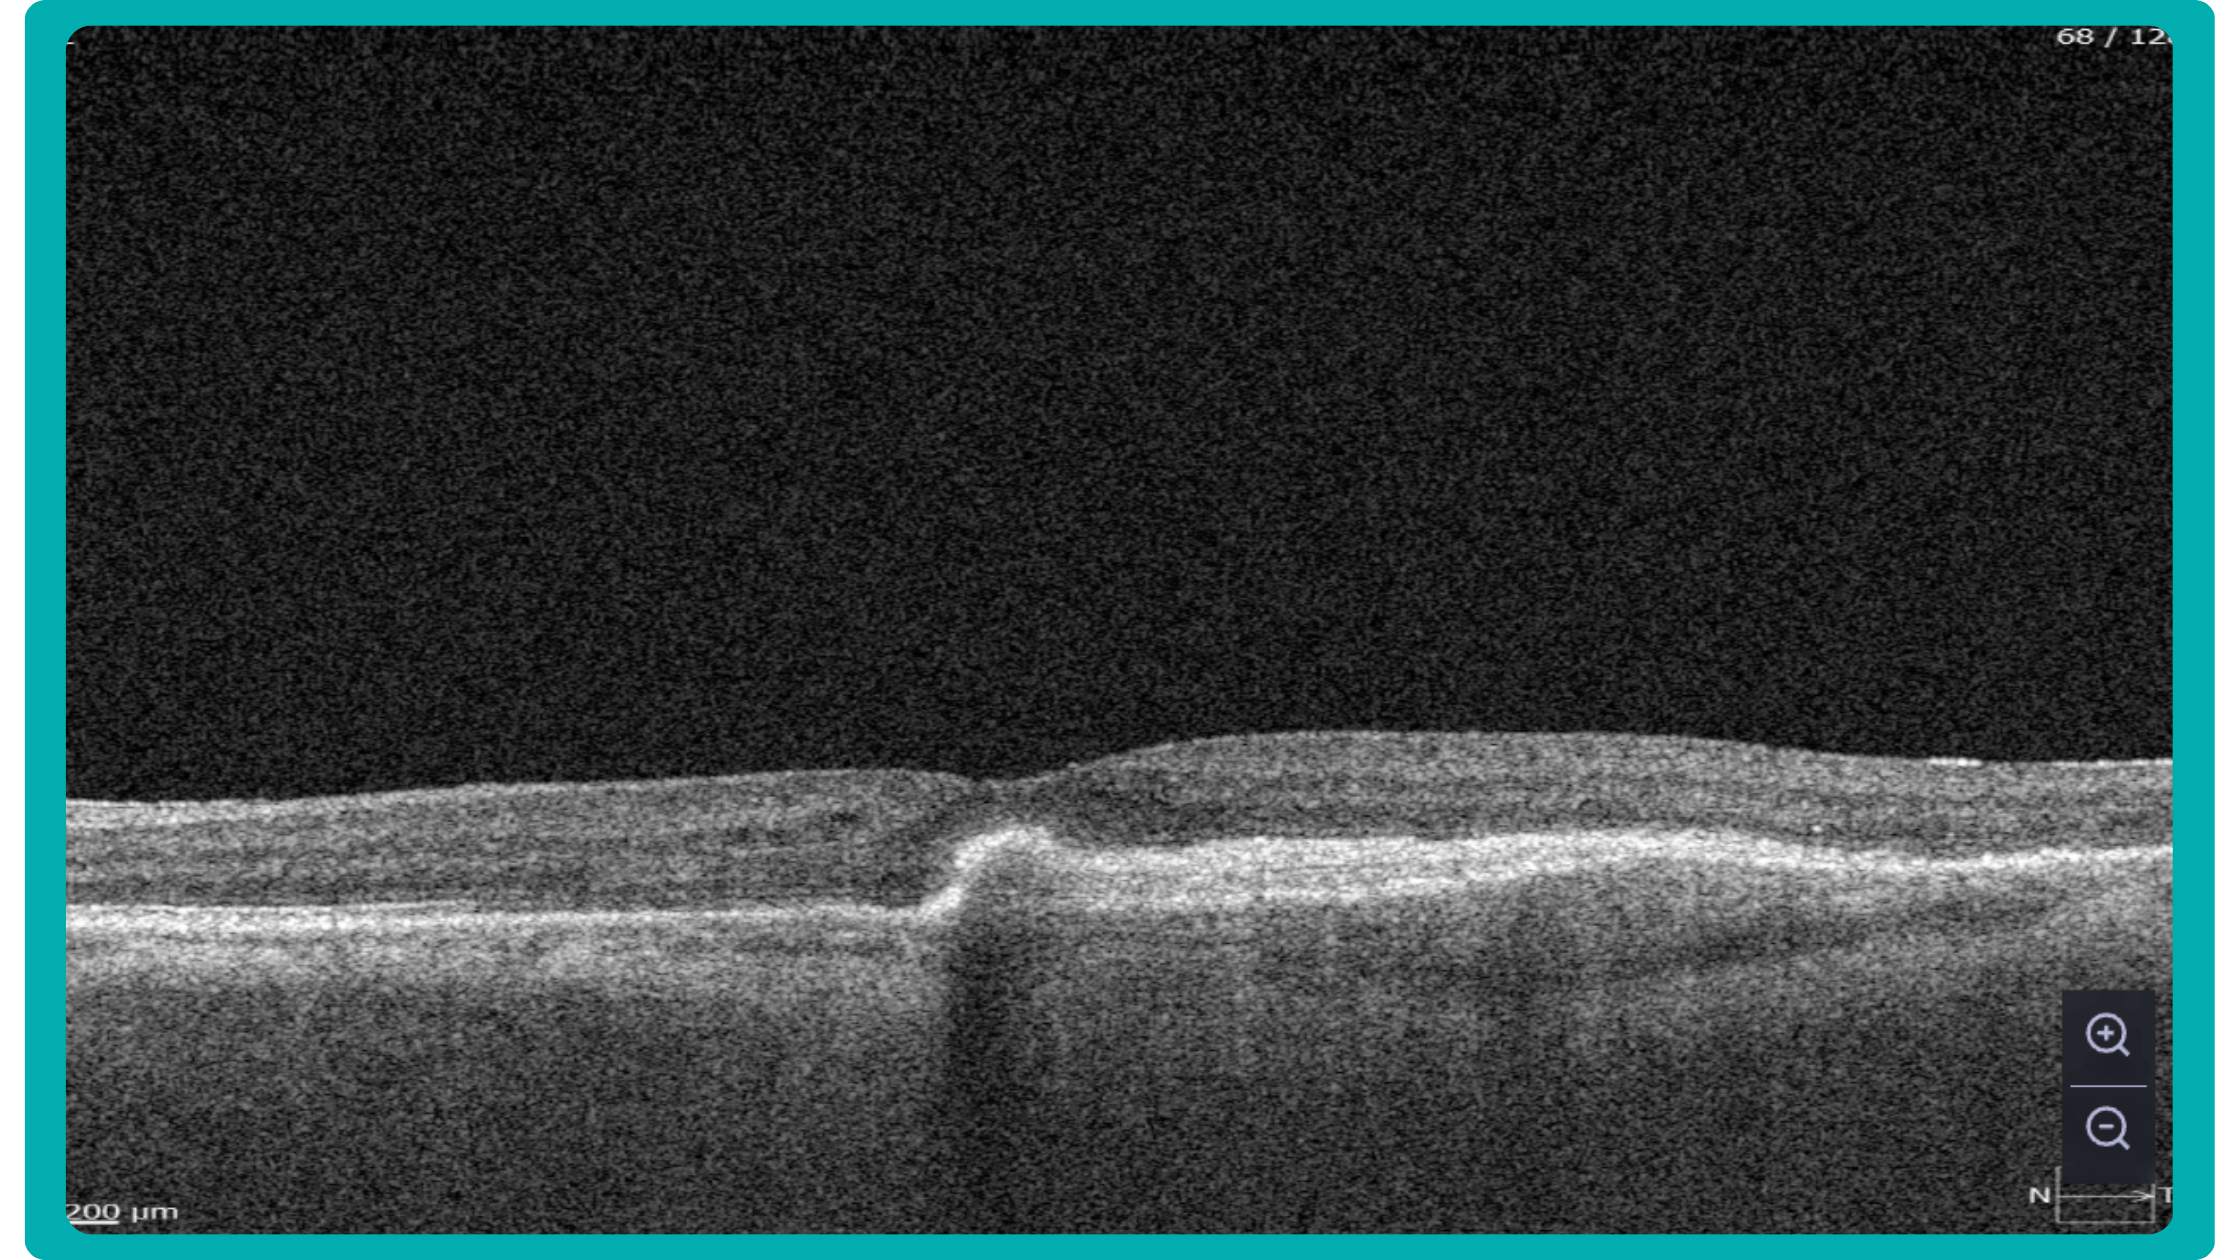

Dr. Maria Sampalis, OD, the owner of Sampalis Eye Care, Rhode Island, utilizes two such programs in her practice. To support her specialization in dry eye management, she employs CSI Dry Eye. Additionally, she uses Altris AI, an AI-powered platform for OCT scan analysis, to provide a second opinion and enhance diagnostic accuracy.

Dr. Sampalis finds that the Dry Eye software allows her and her staff to analyze symptoms and images comprehensively, improving patient care, time savings, and increasing diagnostic precision. See how OCT AI works here.

Her patients also appreciate Altris AI, which analyzes OCT scans for over 70 pathologies and biomarkers while also calculating the risk of developing glaucoma.

Working with specialized software solutions improves diagnostic accuracy and aids in patient education. Visual representations of their conditions, facilitated by these technologies, empower patients with a clearer understanding, leading to increased treatment compliance.

Eye Place, an optometry center in Columbia, also leverages Altris AI, among other cutting-edge technologies. They capture images using the Topcon Maestro2 OCT and use Image Net6 software to export DICOM files to the Altris AI platform.